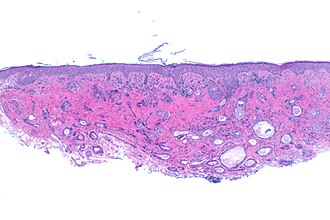

The eyelid is occasionally sent to pathology. Information about the eye is found in the eye article.